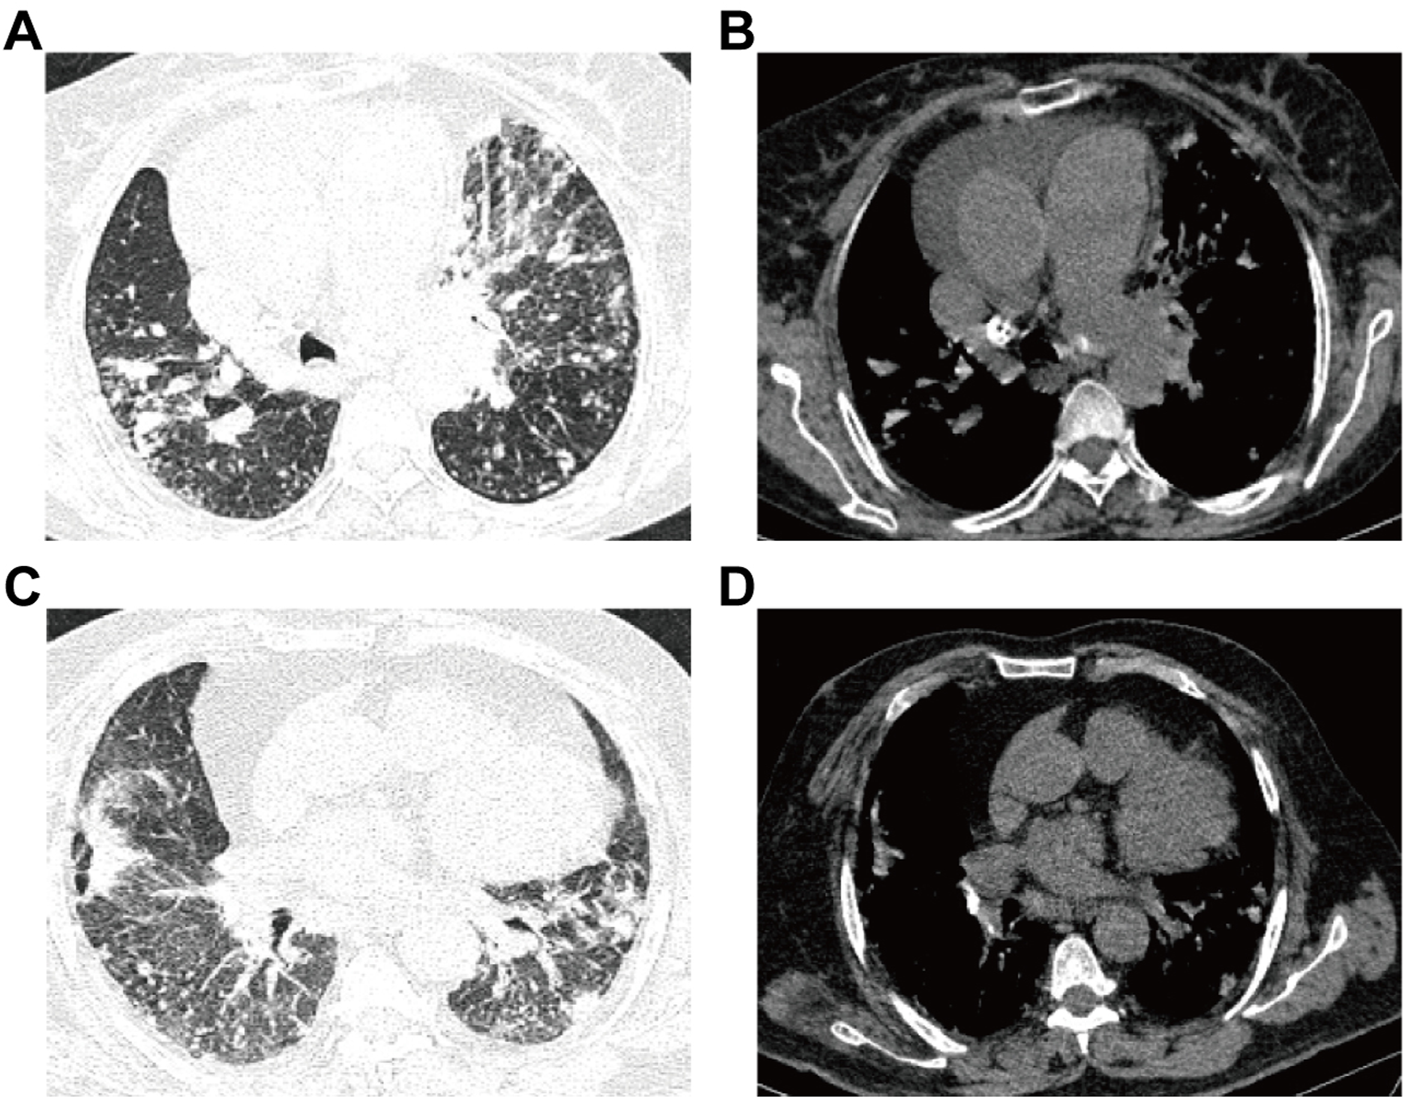

CT scans were completed by using a Siemens CT scanner with a conventional layer thickness of 10 mm, a layer spacing of 10 mm, a thin layer thickness of 2–3 mm, a layer spacing of 2–3 mm, a table feed speed of 5 mm/s, a voltage of 120 kV, and a current of 180–240 mA. For the procedure, the patient was placed in the supine position with the arms raised, and the entire lung was scanned with a layer thickness and layer spacing of 5 mm each, followed by post-reconstruction with a layer thickness of 0.625 mm. The images were checked through both the lung window and the mediastinal window to ensure the quality of the images (Figure 2).

FIGURE 2

Images for ATB and non-ATB. (A–B) Patient with active pulmonary TB: male, 60-years-old, chest pain and dyspnea for 3 days, multiple central lobular nodules in the right lower lobe, left upper lobe and left lower lobe, and with cords and surrounding patchy dense shadowing. (C–D) Patient with non-active pulmonary TB: female, 50-years-old who experienced cough and sputum for 6 days, with multiple patchy shadows observed in the middle lobe of the right lung and the lower lobes of both lungs, adjacent to the pulmonary nodules and surrounded by tree buds.